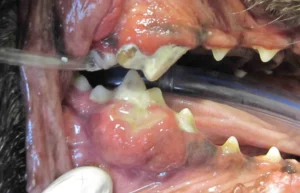

Epulis ” refers to any tumor or growth of the gingiva (i.e. gum tissue). In fact, an epulis can be a non-cancerous growth that occurs as a result of chronic irritation. Historically, three main types of are described in dogs: fibromatous, ossifying, and acanthomatous.Treatment depends on the exact kind of growth so it is very important that any epulis is biopsied.

Odontogenic tumors and cysts are oral growths that develop from dental tissues. They are not considered malignant and they do not usually metastasize or spread to distant organs like the lung or brain. Some of the tumors can be very aggressive locally, and some like to invade into bone and surrounding teeth.

Cheek chewers granuloma is non-cancerous tissue swelling caused by self-inflicted trauma when chewing.  The thickened areas are usually located at the inner cheek lining or the underside of the tongue edges. The condition is seen most often in small dogs with a tendency to bark; however, the lesions can be found in other types of canines or cats.  Therapy is directed at surgically debulking the tissue to prevent further trauma.  Tissue should be biopsied to rule out other tumors including eosinophilic granuloma, a great mimicker of cheek chewers lesions.